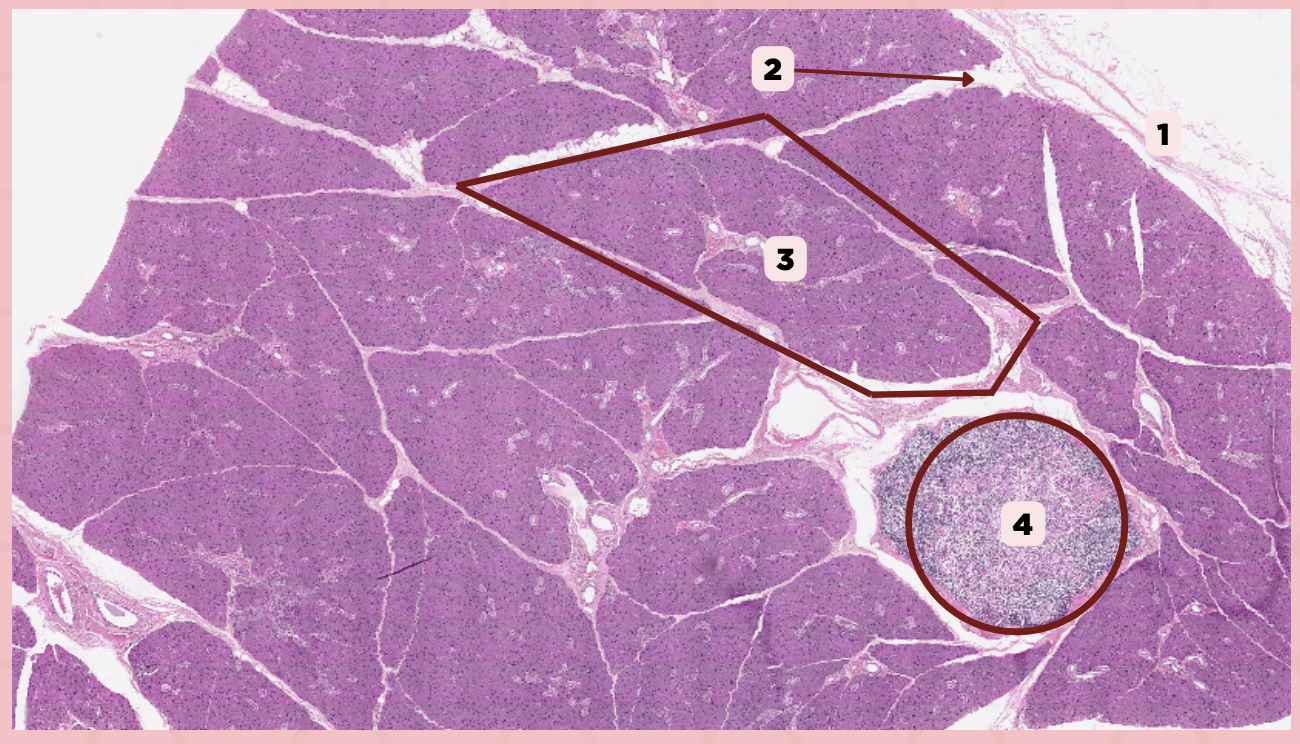

Parotid

Identify the specimen.

Capsule

Identify the structure labeled as 1.

Septa

Identify the structure labeled as 2.

Lobule

Identify the structure labeled as 3.

Lymph Node

Identify the structure labeled as 4.

C) Septa

Which of the following structures shown delineate the lobes and lobules of the parotid gland?

A) Capsule

B) Lobule

C) Septa

D) Lymph Nodes

A) Capsule

Which of the following structures encapsulates the parotid gland?

A) Capsule

B) Lobule

C) Septa

D) Lymph Nodes